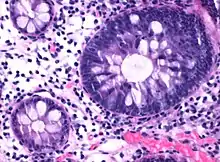

Normal (left) versus dysplastic (large at right) colonic crypts, the latter conferring a diagnosis of a tubular and/or villous adenoma.

Normal (left) versus dysplastic (large at right) colonic crypts, the latter conferring a diagnosis of a tubular and/or villous adenoma. Histopathology of high-grade dysplasia in a tubulovillous adenoma, in this case seen mainly as loss of cell polarity, as cells become more plump and haphazard than the elongated and parallel nuclei of surrounding low-grade dysplasia.

Histopathology of high-grade dysplasia in a tubulovillous adenoma, in this case seen mainly as loss of cell polarity, as cells become more plump and haphazard than the elongated and parallel nuclei of surrounding low-grade dysplasia.